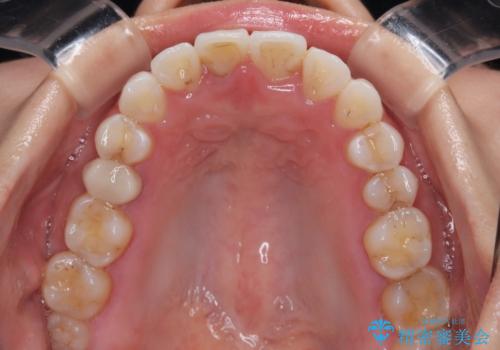

捻れた前歯を楽して改善 ワイヤー装置での非抜歯矯正

- 上下前歯のデコボコを気にして来院された患者様です。

ワイヤー矯正でもマウスピース矯正でも可能でしたが、短期間で、自身の手を煩わせることなく治療を行いたいとのことで、ワイヤー装置にて矯正治療を行うこととしました。

ご本人の中では2年近くかかるものと思っていたそうですが、1年で治療を終えることができ、大変満足していらっしゃいました。